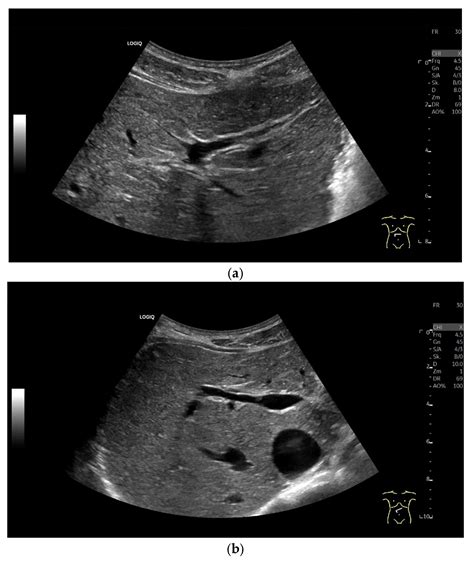

Defining a individual "normal" size for the common bile duct can be nuanced, as it incline to alter based on several ingredient, including the patient's age and whether they have previously undergo a cholecystectomy (gallbladder remotion). However, clinicians bank on standard ambit during symptomatic imaging, such as abdominal ultrasounds, CT rake, or MRCPs.

In a salubrious adult with an inviolate gallbladder, the common bile canal normal sizing is mostly considered to be 6 millimeter (mm) or less. Mensuration are typically taken at the widest point of the duct. If a channel measures slimly above this, physicians look at the clinical context to determine if it represents a variation of normal or a mark of obstruction.

• Imaging Mood: The proficiency used to quantify the duct can charm the termination. Echography is the most mutual first-line trial, but it is operator-dependent. MRI (specifically MRCP) is take the gold touchstone for high-resolution imagination of the biliary tree.

• common bile canal size ultrasound